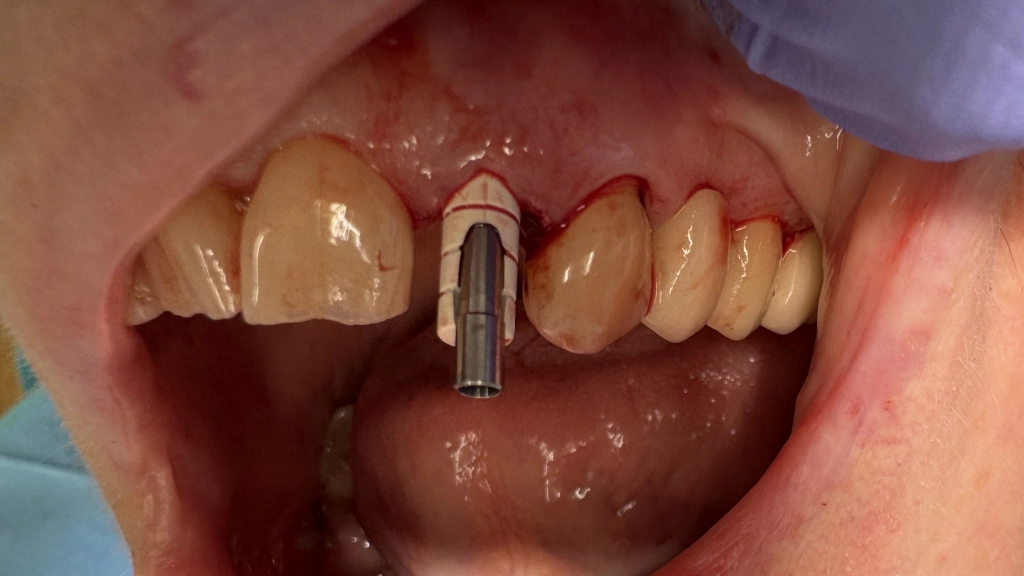

De tandarts plaatst een tijdelijk abutment:

We hebben reeds een kapje voorbereid voor de vorm, het kapje wordt vastgezet aan de witte stift en afgewerkt/gepolijst:

Van dichtbij oogt zo'n noodkroon niet erg fraai, onthoud dat het een stukje plastic is. Op gespreksafstand oogt de tand wel normaal en eerlijk gezegd toch wat netter dan zo'n missende tand!